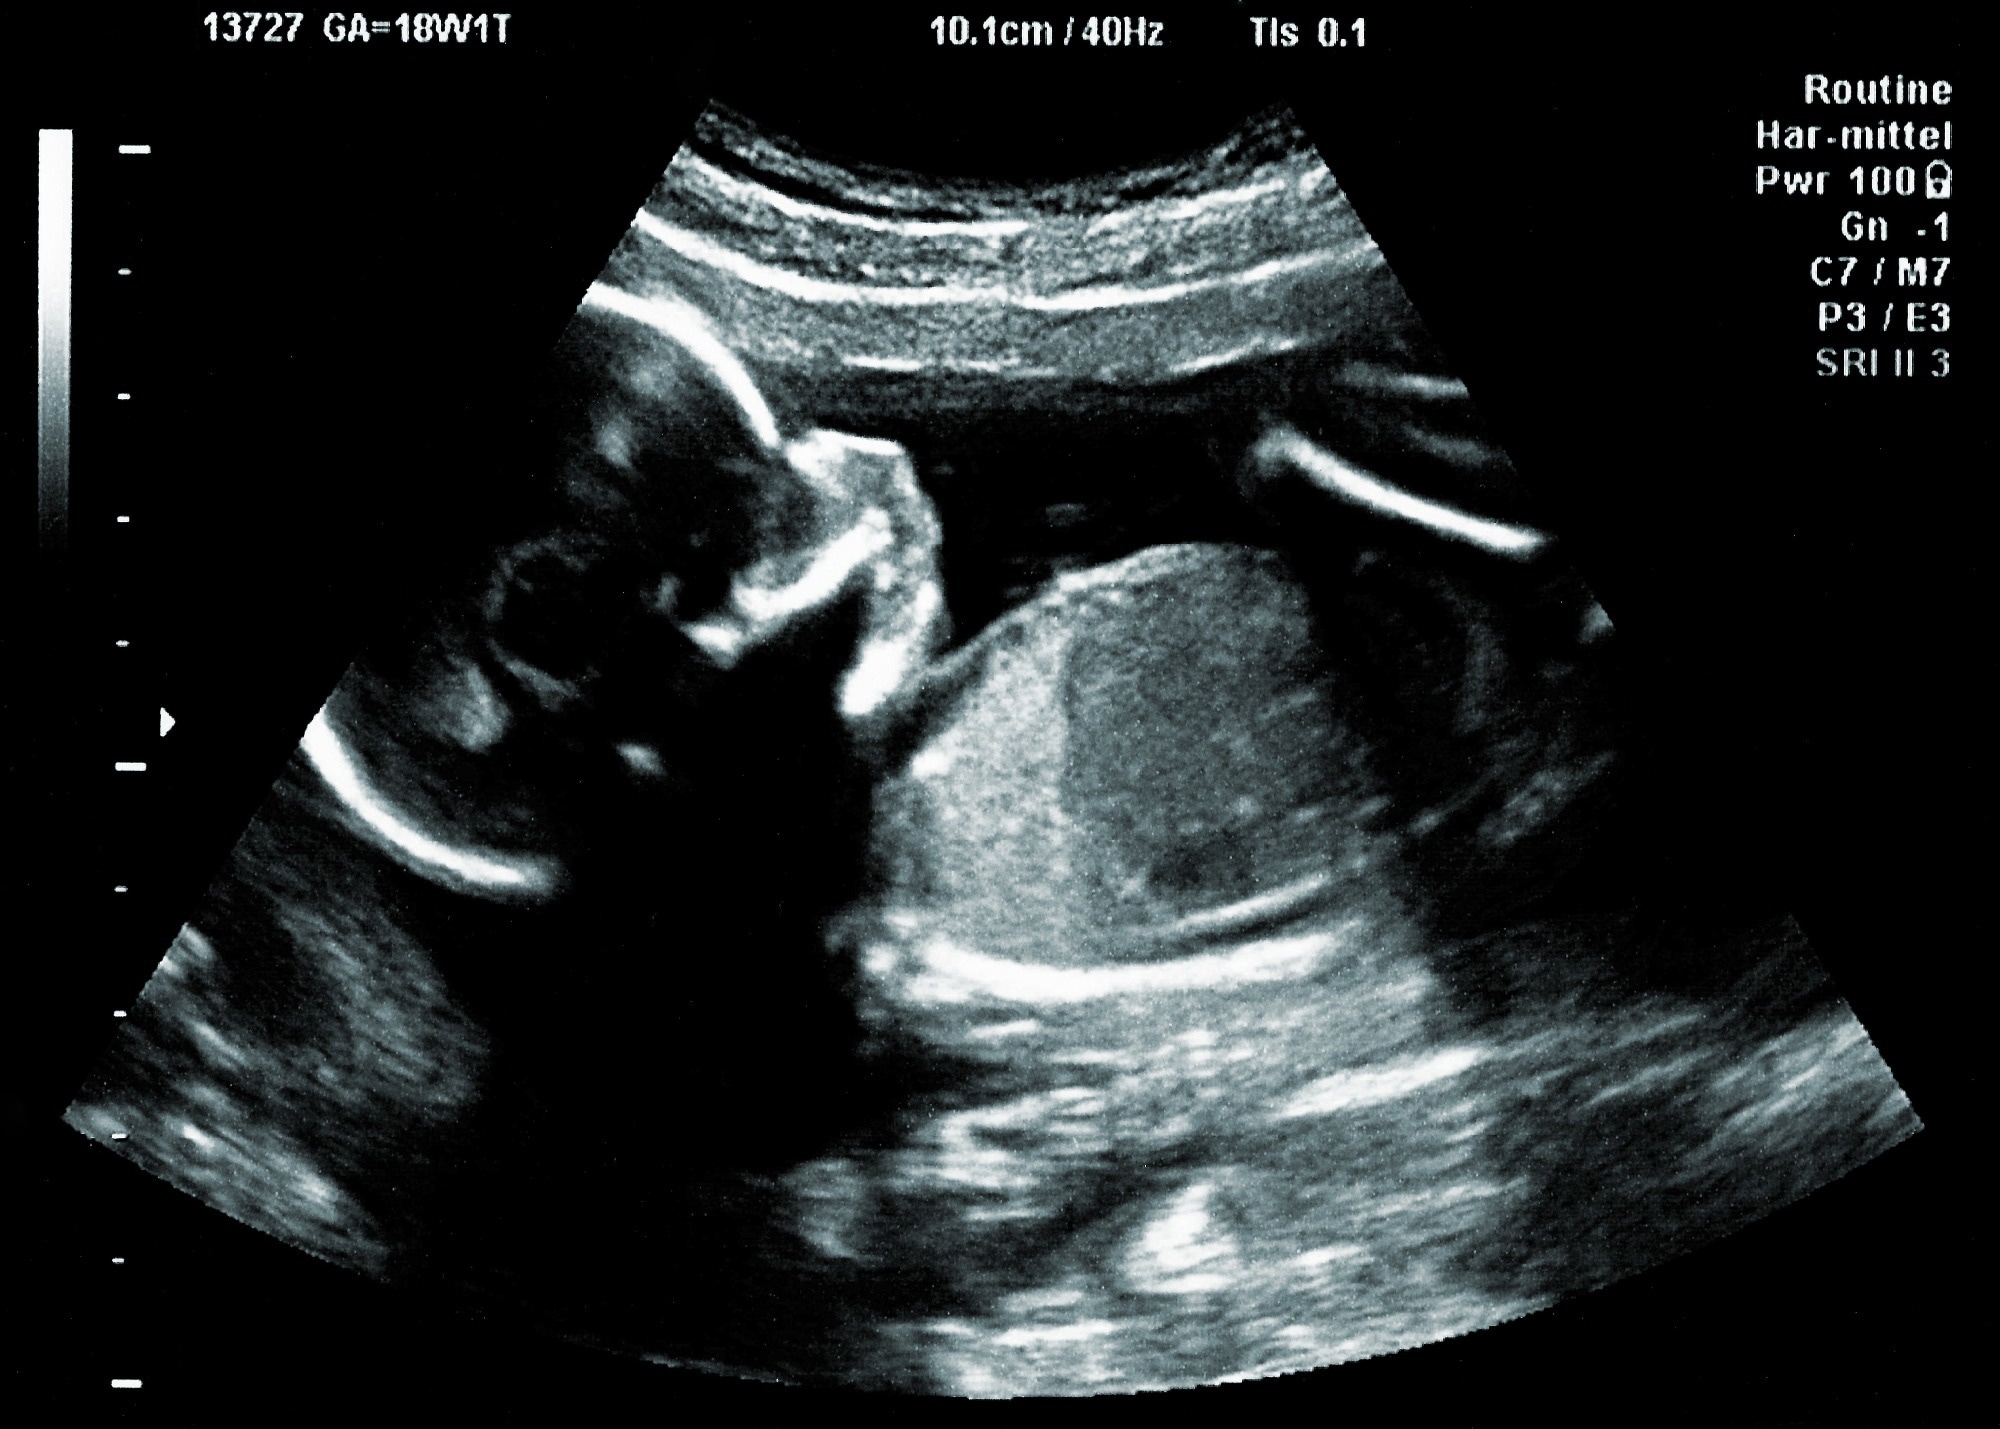

Study: Placental nanoparticle-mediated IGF1 gene therapy corrects fetal growth restriction in a guinea pig model. Image Credit: r.classen / Shutterstock.com